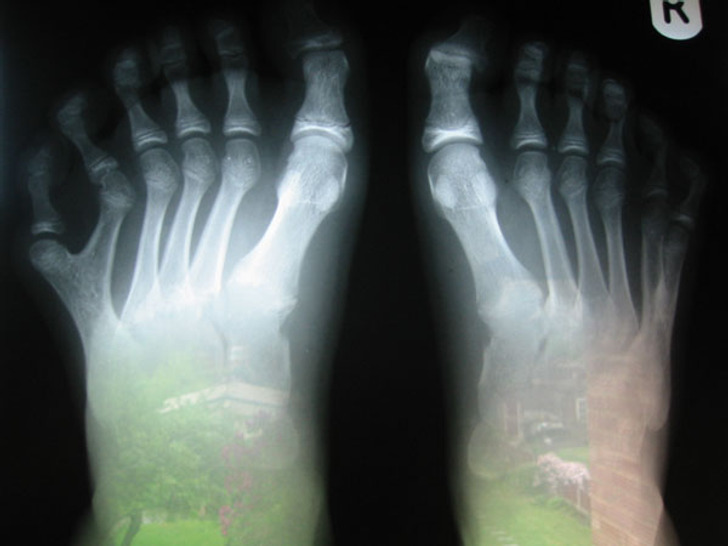

1. Un jeune homme doté de deux orteils au même pied

Illustration de l'article : Ces 18 photos de particularités trouvées chez l'homme et dans la nature

© Unknown user / Reddit

7. Un enfant né avec deux orteils en plus

© cadex / Reddit